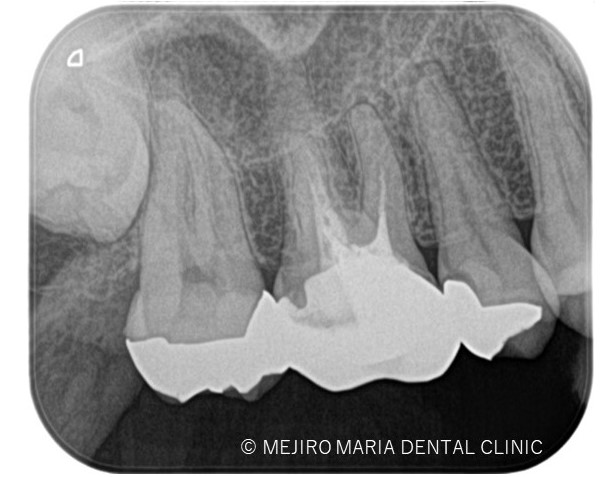

右上の歯牙を4本(右上第一小臼歯〜第二大臼歯)診査したところ、5番には明らかな根尖病変は確認ができません。

しかしながら、歯髄診断を行うと右上5番の歯髄に生活歯髄反応はみられず、歯髄壊死を起因とする根尖性歯周炎の診断に至りました。

診査の結果、右上5番の歯髄には歯髄生活反応は確認できず、歯髄壊死が起因となる根尖性歯周炎と診断しました。術前のレントゲン診査により、根尖が2つに分岐していることを確認できます。